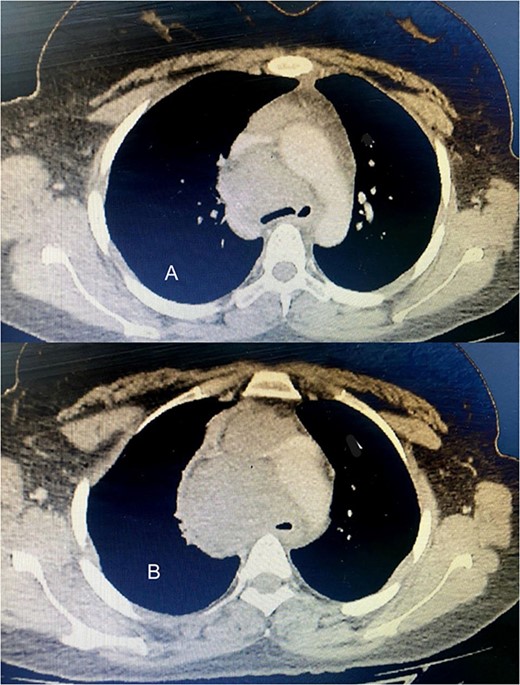

Six chemotherapy courses were instituted, comprising doxorubicin (75 mg/m2) and ifosfamide (7.5 mg/m2) every 3 weeks. Unfortunately, they failed to yield improvement; instead, the mass continued to enlarge. CT-guided injection of the neck and chest revealed a formidable, heterogeneous, hypodense mass with calcifications, measuring 10 × 9 × 15 cm, predominantly occupying the thyroid space and infiltrating adjacent structures, including the right common carotid artery and innominate vein (Fig. 2). A second surgical intervention was imperative, involving a wide Kocher incision (Fig. 3) under general anesthesia. Intraoperatively, the mass was identified as infiltrating the right common carotid artery and innominate vein, necessitating meticulous dissection and shear deployment. The mass extended to the trachea and carina tracheae, prompting careful removal following exposure and isolation of the right and left phrenic nerves.

(A) The tumor extends up to the tracheal carina and compresses on the aortic arch; (B) a tumor in the mediastinum closes the trachea almost completely, deflects it toward the left, and infiltrates the aortic arch and the vena cava.